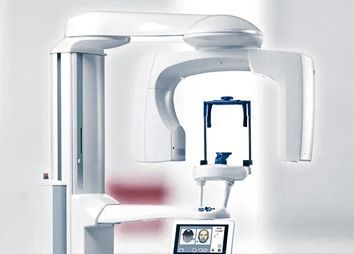

Наше оборудование